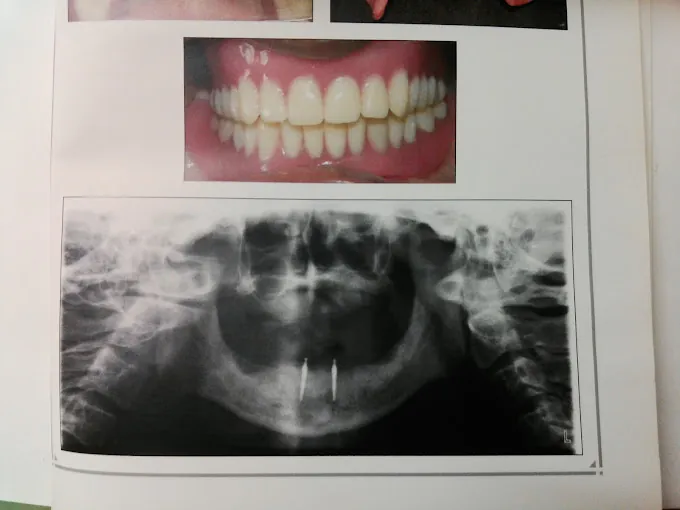

Shifa Dental Multispeciality Clinic In Chennai

At Shifa Dental Multispeciality Clinic in Chennai, we provide exceptional general dentistry, from cleanings to crowns. Our skilled team uses advanced technology to ensure lasting oral health. Open Open daily from 7:30 pm to 7:30 pm, contact us via or Connect on social media. Schedule your visit now!

We use digital imaging for precise diagnostics.